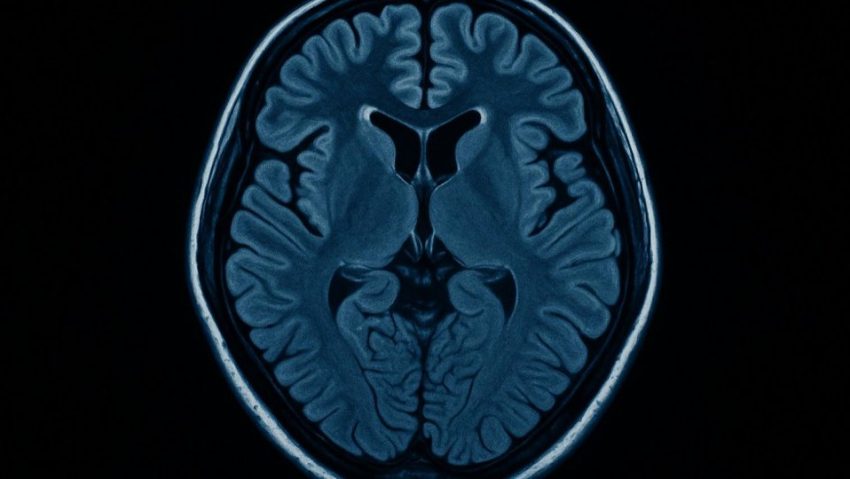

Cercetătorii japonezi au identificat cauza biologică a „ceții cerebrale” post-Covid

Echipa de la Universitatea Municipală Yokohama a descoperit că persoanele care suferă de „Long Covid” prezintă creșteri semnificative ale activității receptorilor AMPA, un tip de molecule esențiale pentru procesele de învățare și memorie.